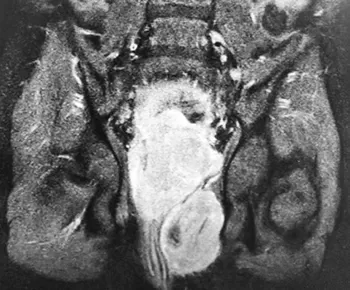

МРТ таза: новообразование больших размеров. МР-картина больше в пользу рабдомиосаркомы, исходящей из предстательной железы с инвазией мочевого пузыря.

Вторичный двусторонний уретерогидронефроз. Состояние после цистостомии (см. рис. 3).

Рисунок 3. Результаты МРТ таза.